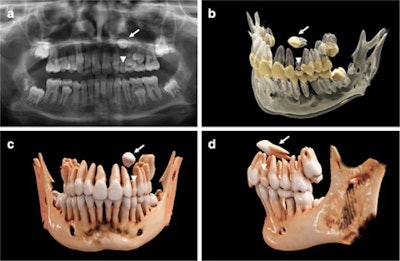

In the report, researchers used cinematic rendering for the volumetric image visualization of midface CT datasets. Predefined reconstruction parameters were specifically modified to visualize complex orthodontic cases in children with ectopic, impacted, and supernumerary teeth. Using the masking and windowing functionality of Siemens Healthineers' Cinematic Anatomy application, upper and lower jaw and respective dentitions were easily segmented, creating natural-appearing images for realistic representations of anatomy, the researchers stated.

"(Nevertheless,) the 3D spatial relationship of the teeth, as well as their structural relationship with the antagonizing dentition, could immediately be investigated and highlighted by separate, interactive 3D visualization after segmentation through windowing," Willershausen and colleagues wrote.